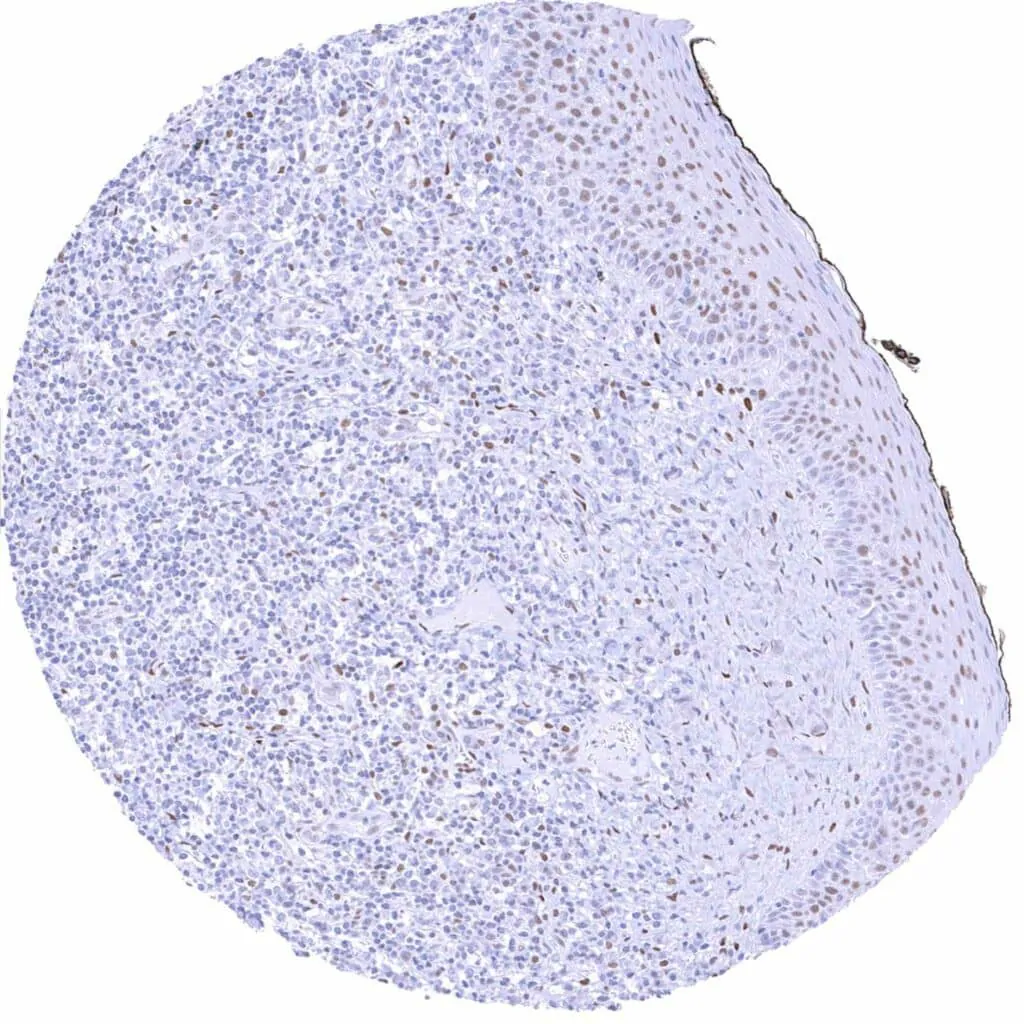

Bone marrow – Weak to strong TLE1 positivity of a significant fraction of cells-1